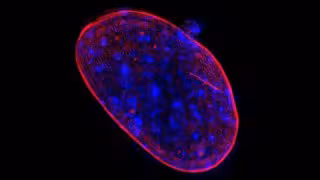

COURTESY OF THE RESEARCHERS